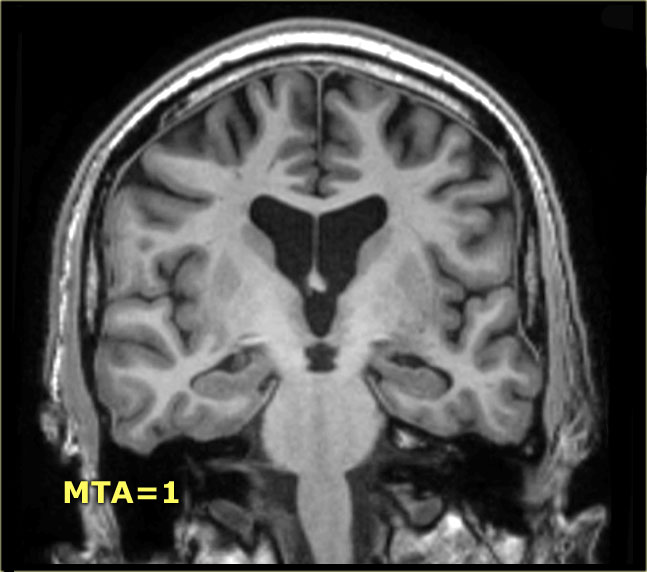

Điểm MTA cần được đánh giá trên chuỗi xung T1W mặt phẳng coronal tại một vị trí lát cắt nhất quán.

Chọn lát cắt qua thân hồi hải mã, ở mức cầu não trước.

Điểm số được tính dựa trên đánh giá trực quan chiều rộng của khe mạch mạc, chiều rộng của sừng thái dương và chiều cao của cấu trúc hồi hải mã.

- Điểm 0: Không có teo não

- Điểm 1: Chỉ giãn rộng khe mạch mạc

- Điểm 2: Kèm theo giãn rộng sừng thái dương của não thất bên

- Điểm 3: Mất thể tích hồi hải mã mức độ vừa (giảm chiều cao)

- Điểm 4: Mất thể tích hồi hải mã mức độ nặng

< 75 tuổi: Điểm từ 2 trở lên là bất thường.

> 75 tuổi: Điểm từ 3 trở lên là bất thường.

Tại đây bạn có thể cuộn qua các hình ảnh minh họa điểm MTA từ 0 đến 4.